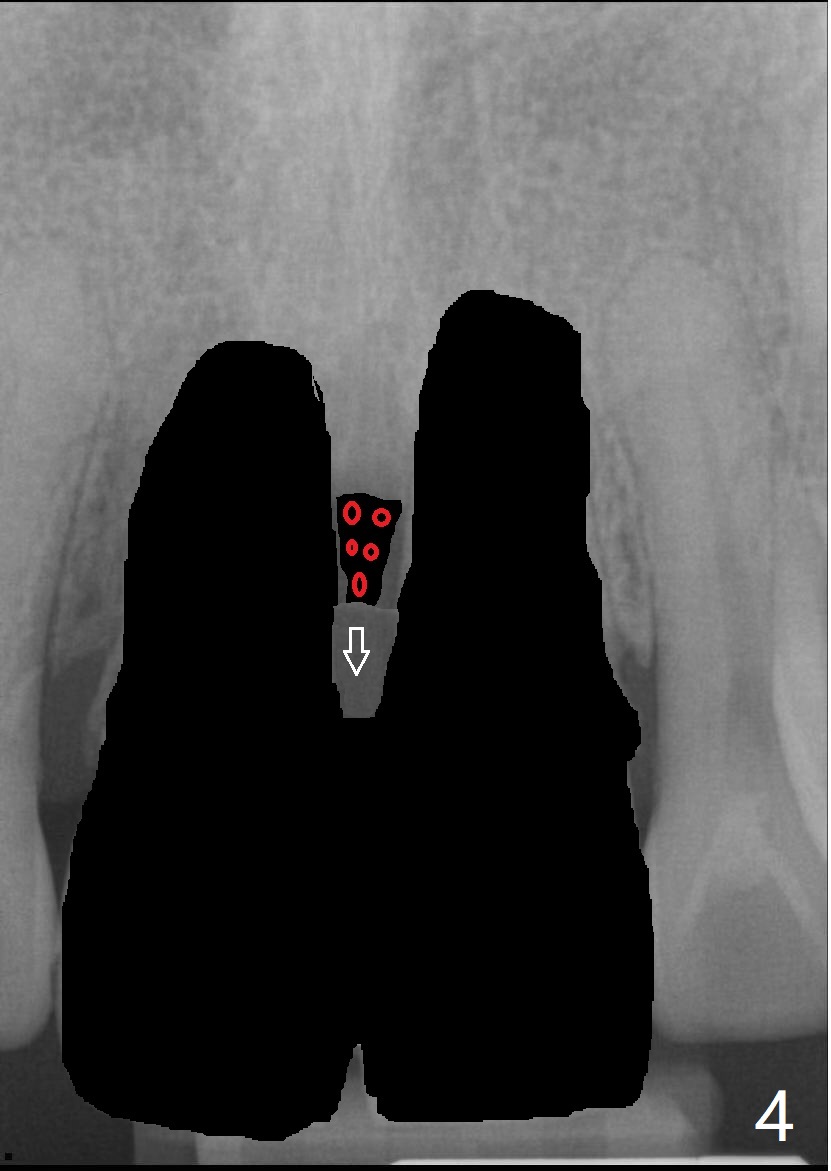

40几岁,身体无其它疾病(图一),全面检查,包括CT,取模做suck down stent/临时牙冠。第一种方法,保留一个牙根(图二:例如8号牙),减少两个牙齿之间软硬组织萎缩,一个植牙(绿色,至鼻底),基台(粉红色),临时悬臂桥,植体周围以及龈乳头下植骨(红圆圈)。图三显示两个牙齿都拔除,P:龈乳头,缺骨。为了在龈乳头下面植骨,分离它的根部,往冠方推移(图四:箭头),在产生的空间里放置骨粉(红圆圈)。也可以在颊侧近中保留部分牙根(socket shield,图五:S),然后游离龈乳头根部,推移,植骨(图六),最后植入两个植体。